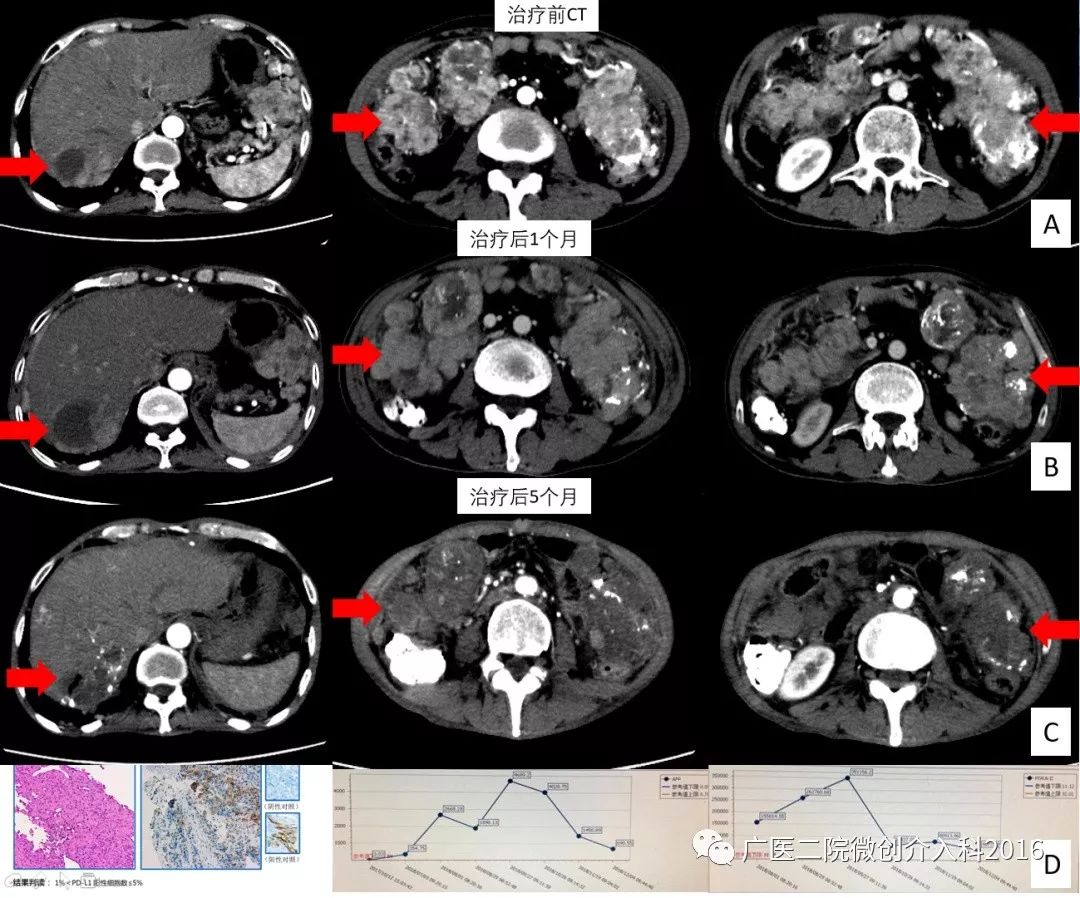

男性,55岁,肝癌晚期。患者因肝破裂在外院行3次肝动脉化疗栓塞(TACE)术,术后进行索拉非尼靶向药物治疗。4个月复查发现腹腔淋巴结广泛种植转移,转移灶血供丰富(图A)。到我科行腹腔淋巴结穿刺活检和基因检测,基因检测结果显示PD-L1表达阳性(图D)、肿瘤突变负荷(TMB)8.6个突变/Mb,靶向药物改为仑伐替尼治疗。我科行腹腔动脉灌注化疗及肿瘤供血动脉栓塞+PD1免疫治疗。治疗后1个月后复查肝内肿瘤、腹腔淋巴结转移病灶较前明显坏死、缩小,肿瘤血供减少(图B);后又经过2次腹腔动脉灌注化疗+3次PD1免疫治疗,5个月后复查肝内肿瘤、腹腔淋巴结转移病灶较前进一步坏死、缩小(图C),肿瘤指标AFP、PIVKA-II较前逐步降低(图D)。现患者介入治疗+免疫治疗已生存11个月。

专家点评

该患者为常规TACE治疗联合索拉非尼后病情进展,原有治疗方法不能继续控制肿瘤。我们在基因检测指导下,使用介入动脉灌注化疗栓塞联合靶向药物+免疫治疗,使患者病情得到有效控制,患者重拾信心。以往遇到这么广泛的腹腔肿瘤转移真的是没有好的治疗手段,免疫治疗的出现,为广大晚期肿瘤患者带来希望!单一PD-1单抗对索拉非尼耐药的患者有效率只有14-20%,该患者联合了介入治疗和靶向治疗,患者肿瘤明显缩小,生存获益。